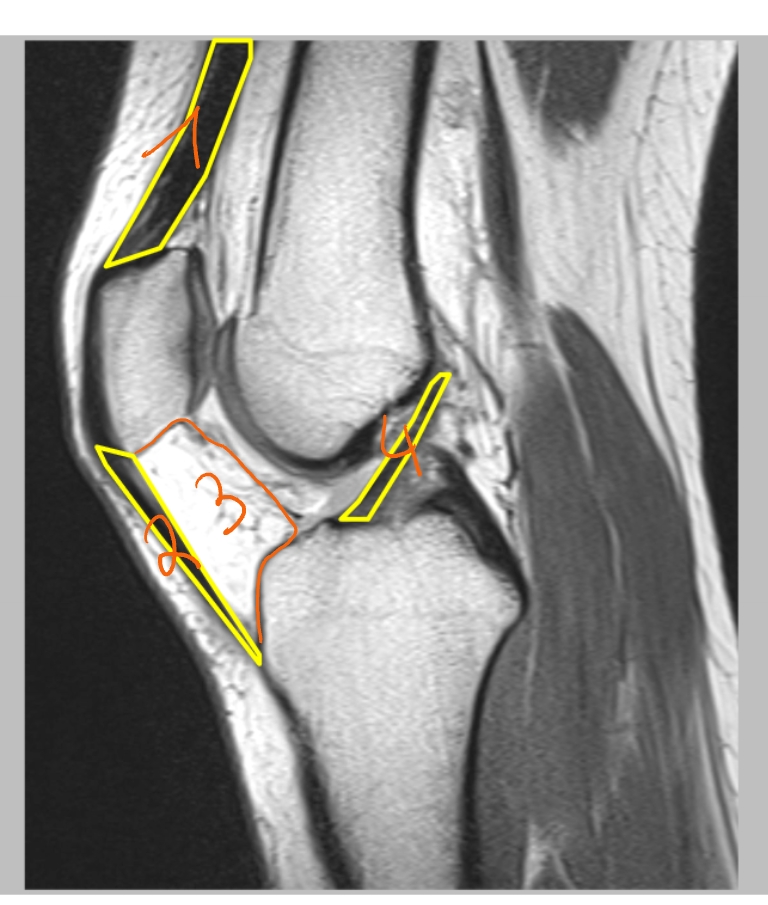

femur

pees van de m. quadriceps

basis patellae

facies articularis van de patella

apex patellae

patellapees/ ligamentum patellae

tuberositas tibiae

fibula

fabella = klein sesambeentje

→ linker knie (MR): dwarse doorsnede

pees van de m. quadriceps

patellapees

vetweefsel van Hoffa

voorste kruisband

achterste kruisband